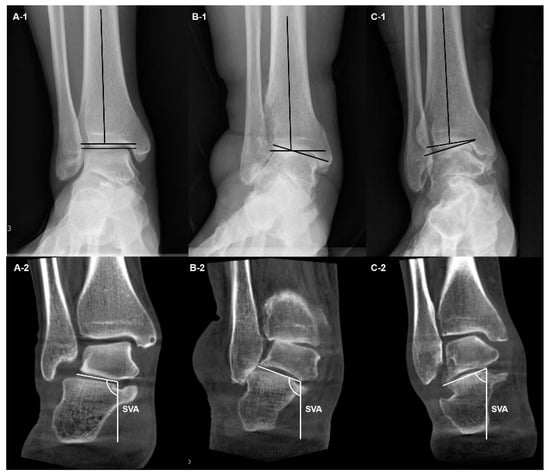

3.1. Ankle Osteoarthritis

3.1.1. Diagnosis

3.1.2. Classification